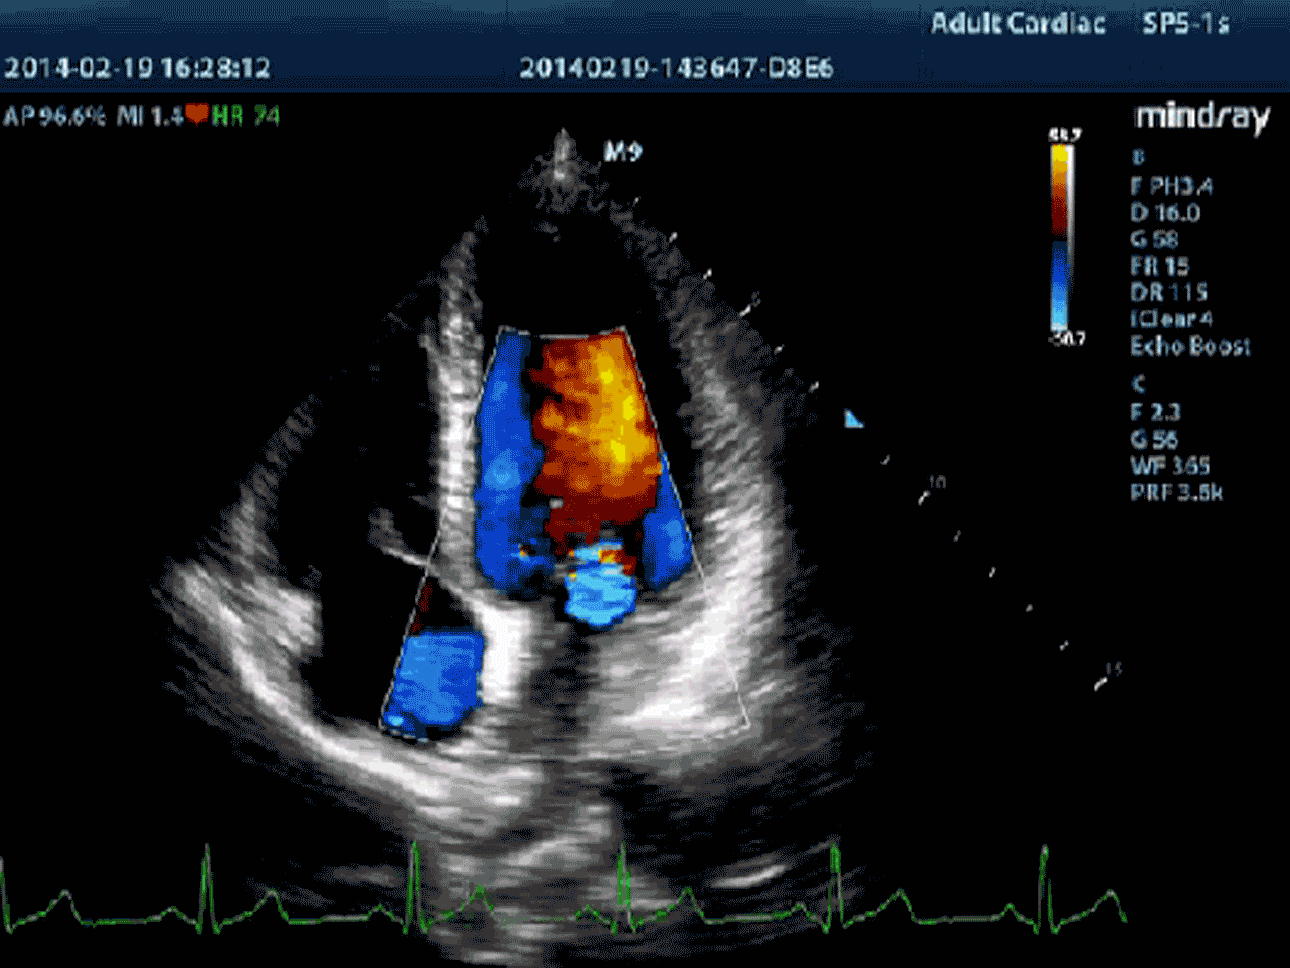

Zaawansowane elementy do przesyłania i odbierania sygnału zapewniają wysoką czułość i dokładność wykrywania echa. Innowacyjne technologie zastosowane w sondach pozwalają na lepszą penetrację i wyższą rozdzielczość, co znacznie poprawia możliwości diagnostyczne.

PSHI™(Phase Shift Harmonic – obrazowanie harmoniczne z przesunięciem fazy)

Funkcja obrazowania harmonicznego zapewnia lepszą rozdzielczość i kontrasowość, dając wyraźniejsze, bardziej klarowne obrazy o doskonałej rozdzielczości i mniejszym poziomie zakłóceń.